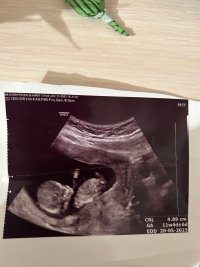

Ramzi teorisine göre bebeğimin cinsiyeti nedir bakar mısınız ?

Kız gibi gördüm hayatım. Resim tarafımdan düzenlendi bilgin olsun. Rabbim hayırlısını versin. Kese yapısı kız gibi duruyor. Tabiki Gaybı bilen sadece Allah'tır. Biz görebildiğimiz kadarını söyleriz sevgiler sunuyorum.

Hayatım sen bana görüntü atmışsın ben sadece kese durumuna göre değerlendirdim. Daha ilerleyen zamanlarda ( ki resimde kesen görünüyordu hayatım ) başka şekilde resim edinir isen tabiki yeniden değerlendirmek isterim.